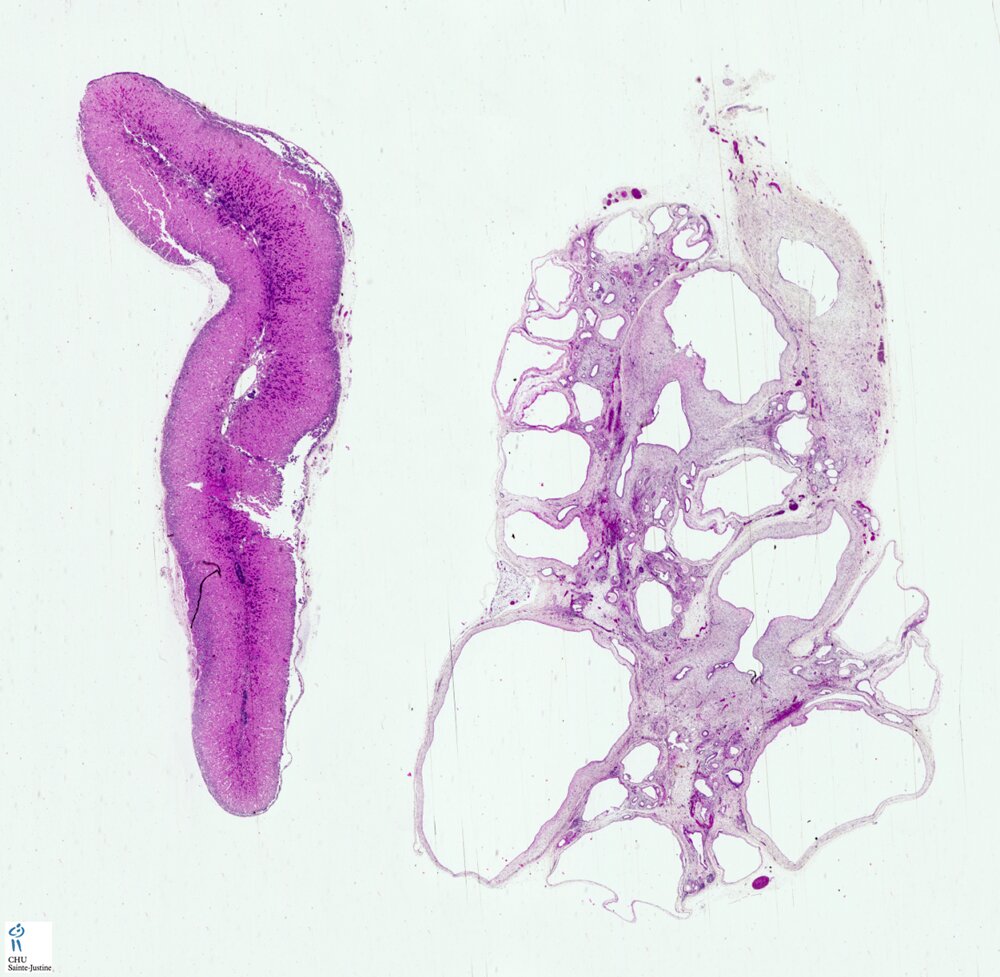

renal adysplasia

Definition: Any combination of renal agenesis (renal aplasia) and non-obstructive renal dysplasia (NORD). An autosomal dominant inheritance is suggested.

cystic dysplasia of the rete testis (16822083)